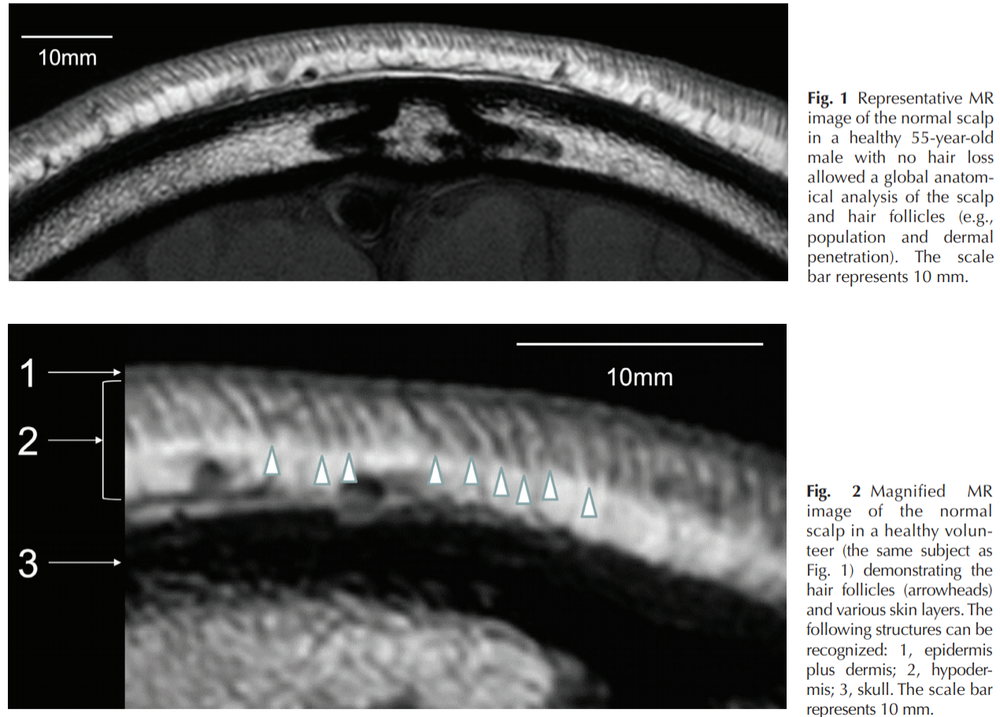

retinoic acid promotes bone profileration at the expense of cartilage(and fats).that crap destroys cartilage, induces autoantigen-homing on the hair follicle outer rooth sheath(and cartilage in the joints)- and is upregulated in balding scalps. ALso, the balding scalp has been shown to be excessively thin when compared to normal hairy scalps in MRI scans.

View attachment 147036

my analysis of this- is that bony layer, the skull(the dark matter in the MRI scan)- replaces the connective tissue above it- n that is loose cartilage. SHH ups SOX(- master regulator chondrogenesis http://genesdev.cshlp.org/content/16/21/2813.full and all things cartilage amd is a direct target of SHH.